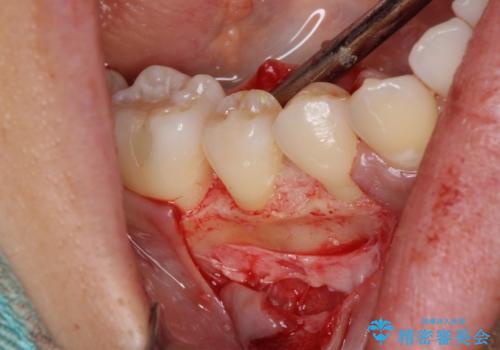

患者様は、他院で右下の歯を抜歯かもと言われました。全体の歯周病はなく、右下の1歯だけ骨が極端に減少していました(初診時歯周ポケット7mm。通常は3mm以下。)。その歯だけ咬合が強いことが原因と考えられたため、咬合を弱くする処置と減少した骨を再生する処置が必要になりました。

骨の再生治療手術をして10か月経過観察をしたのち、骨を平坦化する手術を行い、治療終了となりました。